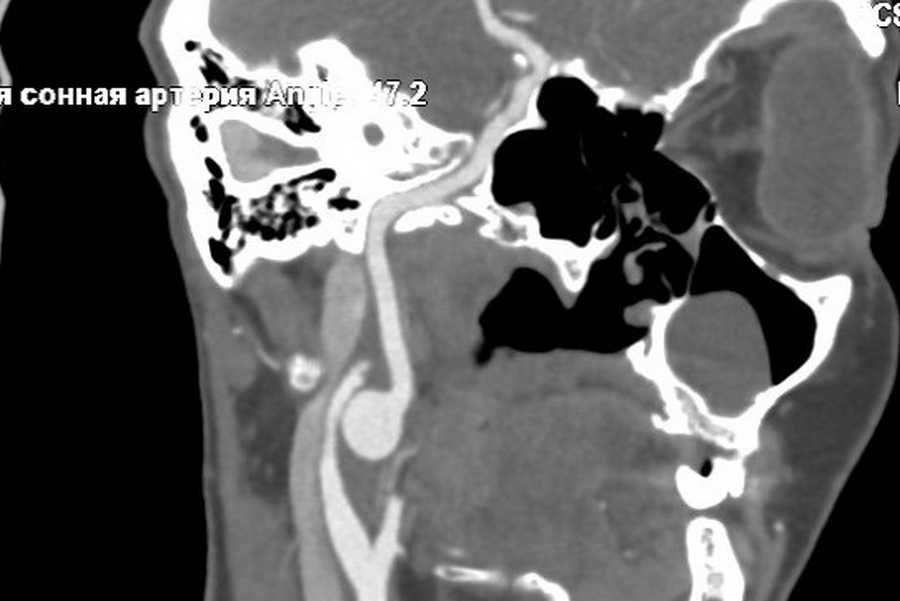

Врачи Федерального центра сердечно-сосудистой хирургии Минздрава РФ г. Красноярск удалили критическое расширение артерии, которое образовалось у пациентки из Хакасии в очень редкой локализации – под углом нижней челюсти, в месте, где сонная артерия входит в череп.

- Сорокапятилетняя женщина в республике Хакассия обратилась по месту жительства к врачу с жалобой на головокружения и головные боли. Специалисты направили ее в федеральный Кардиоцентр Красноярска, где при обследовании выяснилось, что у пациентки жизнеугрожающее расширение сонной артерии – аневризма размером полтора на полтора сантиметра. Такая патология опасна разрывом аневризмы, что приводит к мгновенной смерти. Ситуация осложнялась местом расположения патологии – в районе угла нижней челюсти, перед входом артерии в череп, - рассказывают в  Федеральном Кардиоцентре Красноярска (ФЦ ССХ) .

- Операция заняла два часа, нам удалось иссечь поврежденный участок артерии, стенка сосуда в области аневризмы была сильно истончена. Пациентке повезло, что она вовремя оказалась в Кардиоцентре, в ближайшее время мог произойти разрыв артерии. Мы наложили анастомоз «конец в конец», это единственный выход в такой ситуации, что опять же не давало нам малейшего шанса на ошибку. Экстракраниальные аневризмы именно такой локализации – редкая и малоизученная проблема. Послеоперационный период прошел без осложнений, пациентка выписана домой, - пояснил сосудистый хирург кардиохирургического отделения №1 Антон Исаев.